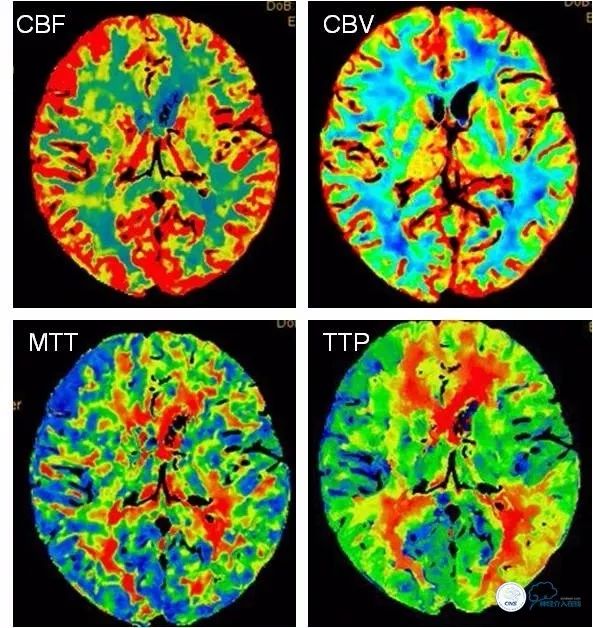

CTA+CTP(2018-4-4):左大脑中动脉支架术后,远端血管分支较对侧减少。左侧半球低灌注,间接提示左大脑中动脉支架术后再狭窄可能(图4,5)。

图4

图5

术后CTA及CTP∶左大脑中动脉球囊扩张术后,远端血管分支及血流灌注较前片相比明显改善(图13,14)。

图13

图14